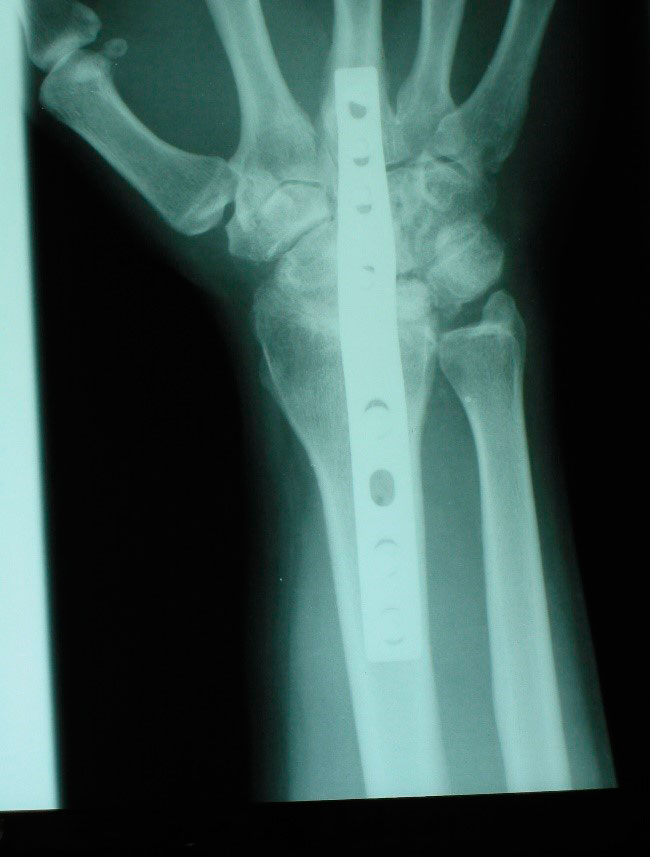

Artrodesis total de muñeca para la enfermedad de Kienböck

La artrodesis total de muñeca como tratamiento de la enfermedad de Kienböck consiste en fusionar el radio con el carpo, de tal manera que se pierde la extensión y flexión de la muñeca (a menudo muy disminuida en los estadios avanzados de Kienböck). Está indicada en pacientes con alta demanda funcional en estadios IIIB y IV. Nosotros optamos en estos casos optamos por esta técnica debido a los buenos resultados en la disminución del dolor y en la ganancia de fuerza (figura 14).

Figura 14: artrodesis total de muñeca sintetizada con placa